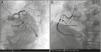

Desensitization was performed without complications and the patient underwent coronary angiography two hours later. This revealed a 90% lesion in the proximal segment of the circumflex artery (Cx) and an extensive lesion in the proximal segment of the right coronary artery (RCA), causing severe subocclusive stenosis, with TIMI 3 flow. Angioplasty of the proximal RCA was performed with placement of two BMS and of the proximal Cx with one BMS (Figure 3).